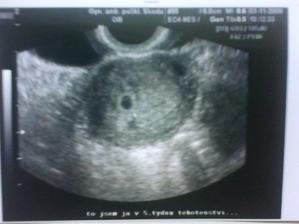

03.11.2009 5.týden potvrzení těhu,kde byli 3 tečky

20.11.2009 7.týden už jen jedna tečka 3mm a máme srdíčko